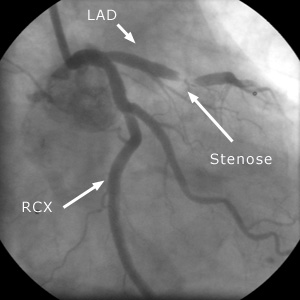

Röntgenbilder der Eröffnung der eingeengten Kranzarterie (Stenose)

mit Ballon und Stent.

Abkürzungen: LAD = Ader zur Vorderwand des Herzens, RCX = Ader zur Seitenwand des Herzens